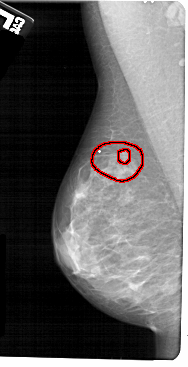

A_1673_1.LEFT_CC

LEFT_CC LINES 5326 PIXELS_PER_LINE 2746 BITS_PER_PIXEL 12 RESOLUTION 43.5 OVERLAY

FILE: A_1673_1.LEFT_CC.OVERLAY

TOTAL_ABNORMALITIES 1

ABNORMALITY 1

LESION_TYPE MASS SHAPE IRREGULAR MARGINS SPICULATED

ASSESSMENT 5

SUBTLETY 4

PATHOLOGY MALIGNANT

TOTAL_OUTLINES 2

BOUNDARY

CORE